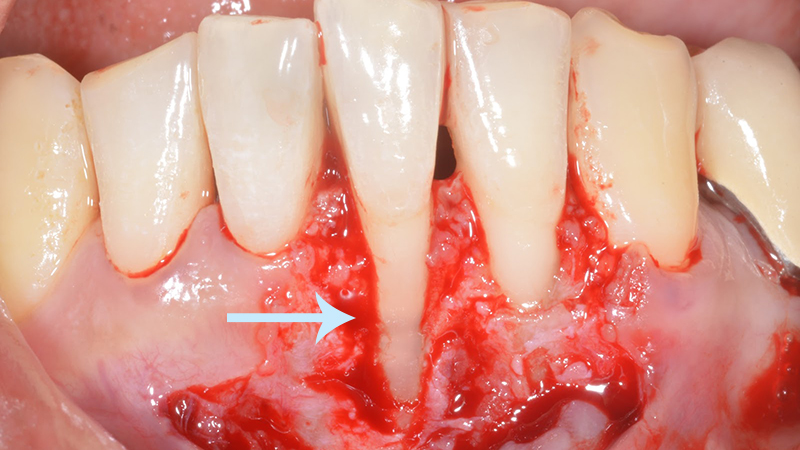

Les interventions chirurgicales comprennent la chirurgie d’accès pour accéder aux zones infectées, les greffes osseuses pour régénérer l’os perdu, le recouvrement radiculaire pour couvrir les racines exposées, l’augmentation du volume gingival pour améliorer l’esthétique, la régénération guidée des tissus pour encourager la croissance cellulaire appropriée, et la chirurgie plastique parodontale pour des fins esthétiques